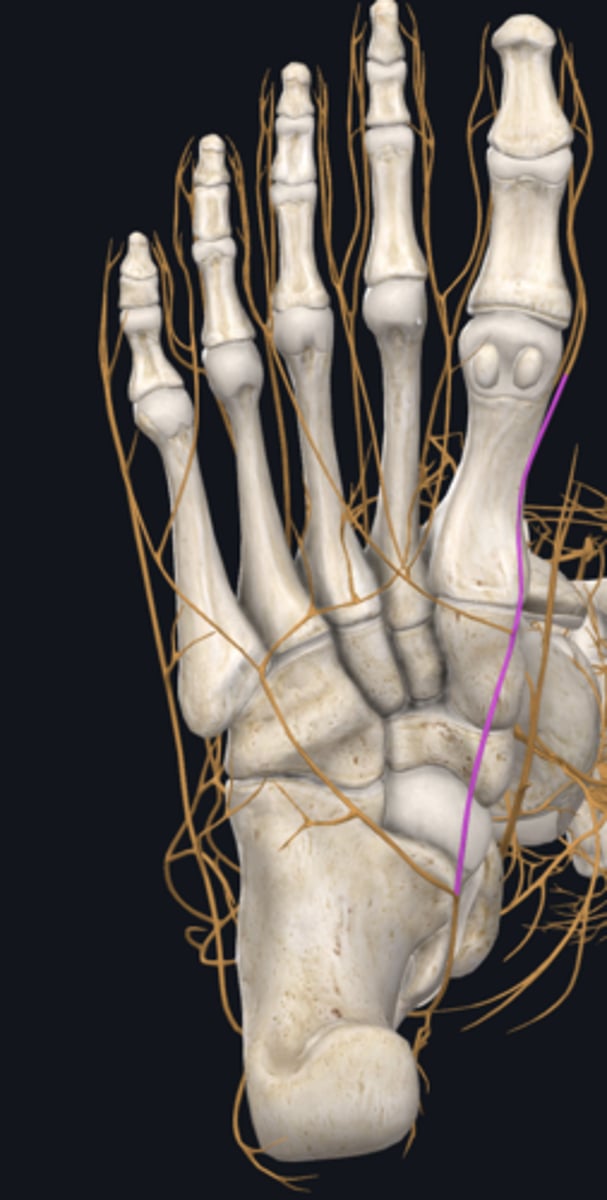

Common fibular nerve

nerve highlighted in pink

Deep fibular nerve

nerve, deep

Superficial fibular nerve

nerve, superficial

Dorsalis pedis artery

Superior extensor retinaculum

Inferior extensor retinaculum